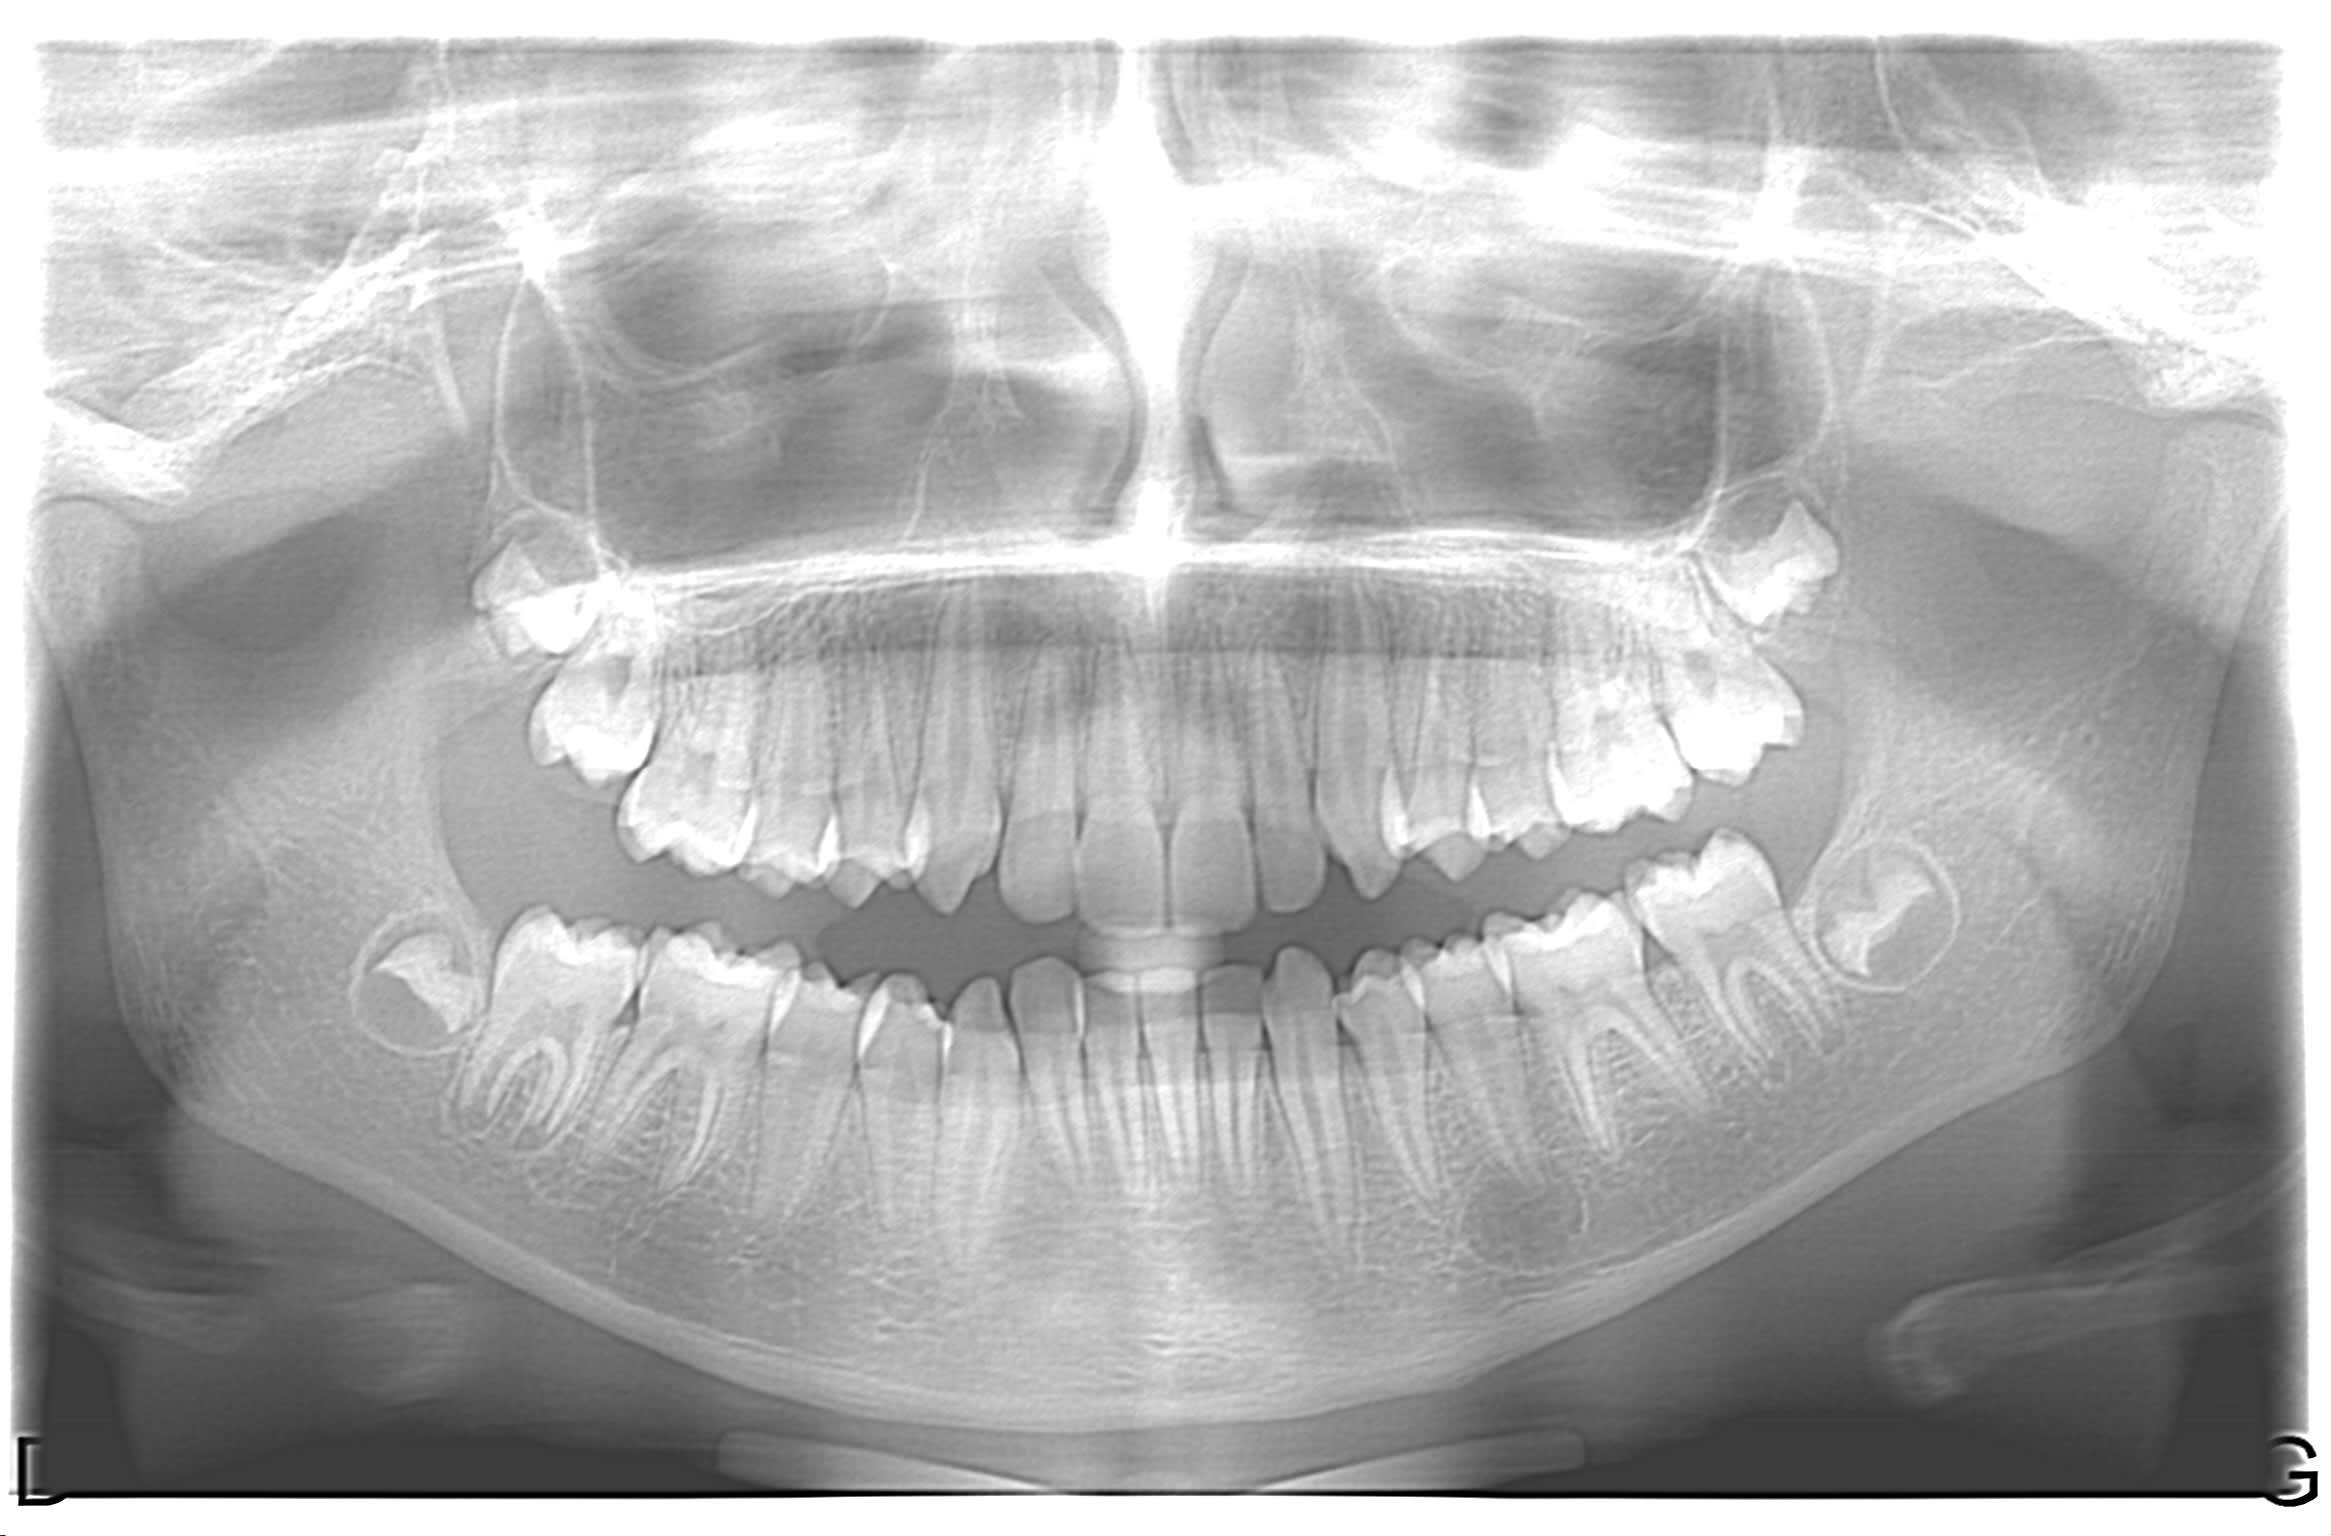

patiente de 11 ans. sans symptôme.au niveau de la 35 apicale, prédence d'une masse hétérogène. vitalité ok.

il n'y a pas de solution de continuité radiologique entre l'espace desmodontal et le périmètre de la lésion qui se superpose à la structure dentaire par un liseré dense.

Un germe surnuméraire? Ca me fait penser à ça, même si c'est évidemment sans certitude.

lacune de stafne!!!!!!!!!!!!!!!

dysplasie fibreuse, neurinome, granulome éosinophile......

il faut une biopsie osseuse et anapath pour savoir. Moi je verrai bien le stade initial d'une dysplasie fibreuse, de toute façon milieu hospitalier pour la fiabilité des anapath si tu ne tombe pas sur un crétin qui veut énucléer d'emblée.

Je ne crois pas du tout à une lacune de Stafne : trop antérieur et l'image scanner d'une lacune n'a rien à voir. Ca donne normalement une dépression de la table linguale de la mandibule en regard de la glande sous-maxillaire (donc normalement plus postérieur).